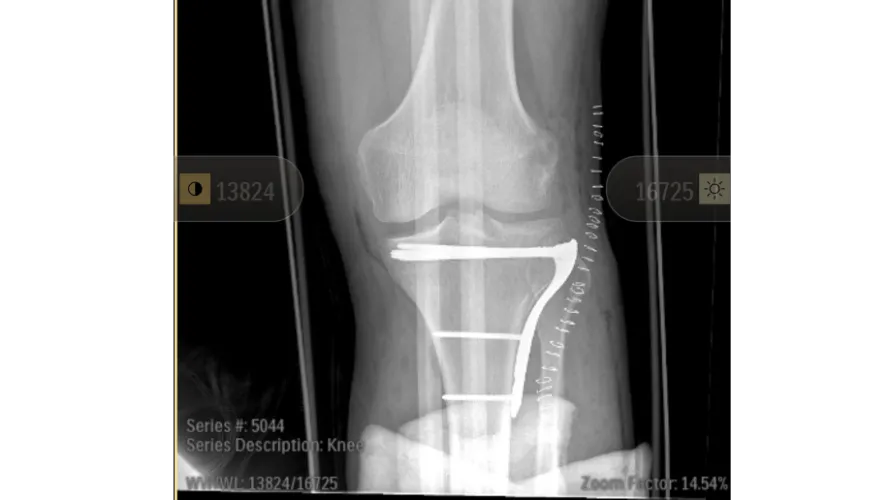

Chris was rushed to the hospital, where he spent four days admitted — two days in the trauma ward and two days recovering post-operation. He suffered a crushed left leg and has already undergone multiple surgeries. Doctors have made it clear that this will be a long road to recovery. They are estimating at least eight months of recovery and rehabilitation. Right now, Chris is in a wheelchair and using a walker as he begins the difficult journey of healing.

Looks like a good job on the tibial plateau fracture. I’ve assisted many such cases with flouro . I’m so glad you are getting the help you need. ✌️❤️